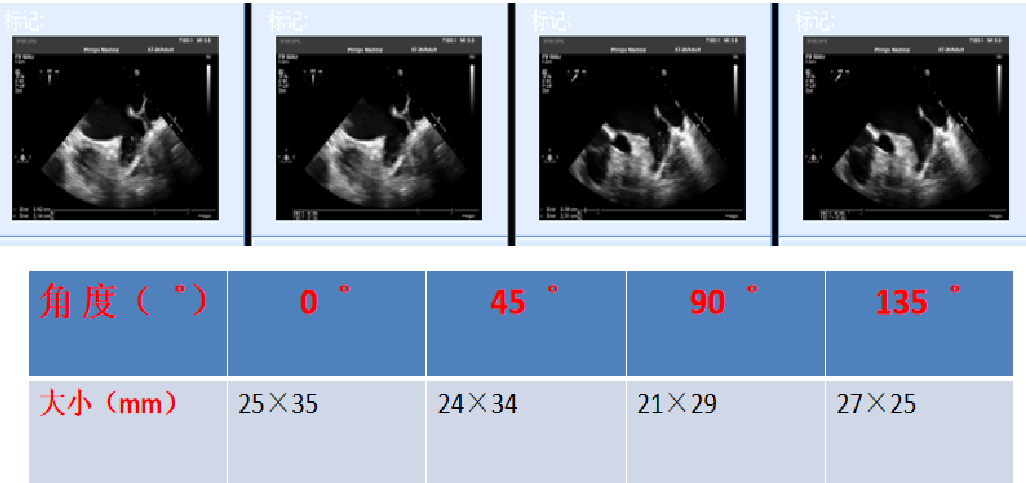

经食道心脏超声左心耳多角度测量